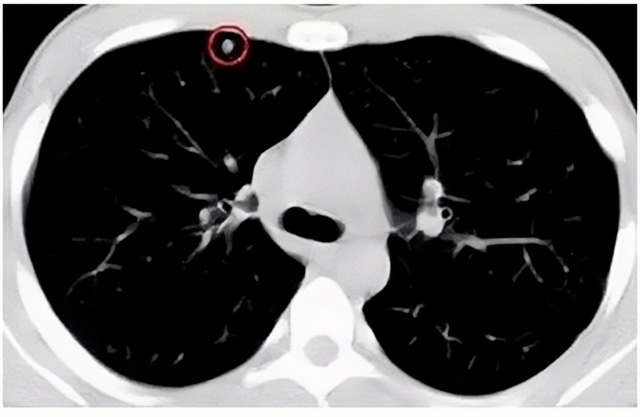

移動(dòng)CT體檢車可以做肺部檢查。隨著多層螺旋CT肺部低劑量掃描的臨床應(yīng)用,目前很多人選擇肺部CT作為常規(guī)檢查項(xiàng)目,較大地提高了肺結(jié)節(jié)的檢出率。如果檢查發(fā)現(xiàn)肺部有肺結(jié)節(jié)是磨玻璃型的,小于5mm的微小結(jié)節(jié),大部分都是良性的。如果達(dá)到1CM以上的,很有可能有肺癌的機(jī)率。根據(jù)其內(nèi)密度不同可分為磨玻璃結(jié)節(jié)、實(shí)性結(jié)節(jié)、部分實(shí)性結(jié)節(jié)。根據(jù)其大小可分為肺大結(jié)節(jié)、小結(jié)節(jié)和微小結(jié)節(jié)。如果是炎癥性肺結(jié)節(jié),幾個(gè)月后復(fù)查有變化變小就不用做手術(shù)。如果CT再次復(fù)查結(jié)節(jié)沒有變化,沒有縮小就需要升級(jí)做病例檢查。病理檢查的確診性是最高的。是有沒患癌的標(biāo)準(zhǔn)。檢查發(fā)現(xiàn)早的話,規(guī)范手術(shù)治療,手術(shù)后5年的存活率很高的。肺癌這個(gè)要早發(fā)現(xiàn)早治療。

現(xiàn)在的移動(dòng)CT體檢車的分辨率比X光高,CT掃描的圖像越來越薄顯像更清晰,檢查更準(zhǔn)確。得到了普及,肺結(jié)節(jié)的測(cè)出率很高的。但是顯浩告訴大家,肺結(jié)節(jié)不等于肺癌。雖然很多是良性,但是很多肺癌都是肺結(jié)節(jié)發(fā)展來的。 必須定期檢查復(fù)查。磨玻璃結(jié)節(jié),肺癌的機(jī)率較高。肺癌是惡性腫瘤病死率最高的。除了環(huán)境,遺傳,等因素。吸煙,從事煙霧工作行業(yè)的人員比較危險(xiǎn)。發(fā)病比例高。肺部疾病早發(fā)現(xiàn)早治療,依舊是肺部疾病的治療標(biāo)準(zhǔn)。

一旦CT檢查發(fā)現(xiàn)肺結(jié)節(jié),若不規(guī)律復(fù)查,檢查等同于白檢。所以在復(fù)查中,如果結(jié)節(jié)中發(fā)現(xiàn)有增大的趨勢(shì),或大小發(fā)生了變化,我們必須提請(qǐng)注意及時(shí)治療,不要掉以輕心。移動(dòng)CT體檢車的普及化,讓肺部檢查更準(zhǔn)確更高效。發(fā)現(xiàn)肺結(jié)節(jié)時(shí),及時(shí)就醫(yī)并進(jìn)行專業(yè)評(píng)估是確保準(zhǔn)確分類和采取適當(dāng)措施的關(guān)鍵。